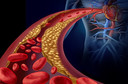

As mulheres tendem a ter volumes de placa1 nas artérias coronárias2 menores do que os homens, mas sua carga total de placa1 é maior porque os depósitos de gordura3 ocupam uma fração maior de suas artérias coronárias2, que são menores. De acordo com um novo estudo publicado na revista Circulation: Cardiovascular Imaging, o risco de ataque cardíaco ou hospitalização por dor no peito4 nas mulheres emergiu quando a carga de placa1 era menor do que a dos homens, e o risco também aumentou mais acentuadamente.